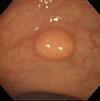

■ 3年ぶりに大腸内視鏡を受けましたが、なんと上行結腸に5mmのポリープが出来ておりました。

下の画像は小生の立派な?我が分身「ポリープ」です。 みなさまも何ら症状がなくとも受けましょうヨ・・・・ 今回、3年ぶり確か5回目の大腸内視鏡(コロノスコピ−)を経験しました。つまり小生が大腸内視鏡を受ける側(被検者・患者)となったのです。

ああ盲腸だなあ これからスコープの引き戻しが始まるなと思った瞬間 現れました ポリ−プが 大きさは5mm前後でしょうか? 側臥位のため通常の見慣れた画像とは90度回転しており、違和感はありますが、紛れも無く小さいながらも立派なポリ−プです・・・ その表面の模様から「腺腫 tubular adenoma 」と自己判断しました。 思わず叫びました。「写真をいっぱいとってくれ 遠景も接近像も さらにNBIも追加」と

NBI(狭域色調強調)画像です ポリ−プ表面はキレイな模様をしているのが明瞭に強調されてます このようなパターンは悪性ではなく、良性なのです。

次はこの可愛い「分身の切除」であります。 これくらいの大きさであれば、鉗子で引きちぎってしまうことができます。小生の場合も、鉗子で採れてしいましたが、何ら引っ張れるとかいう感覚はまったくありませんでした(ちなみに胃の生検をされた経験もありますが、この際は摘んで引っ張られる感覚はありました)。 にじむ程度の出血はありましたが、ポリ−プは完全にとれてしまい治療も完了です(後日の顕微鏡での検索でも予想通り「腺腫」)。